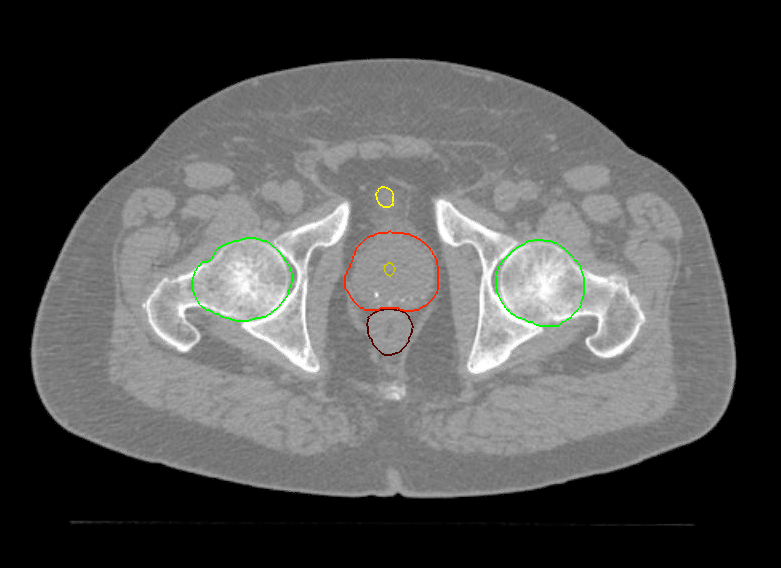

Planning CT Images